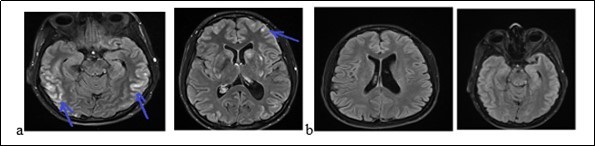

Mrs. A.S., a woman of 56, was admitted to hospital on february 9, 2018 for gradual onset in a three week, confusion, intense and diffuse headache with vomiting and photophobia. She treated the headache in automedication with a non-steroidal anti-inflammatory drug (NSAID, ibuprofen). The symptoms had worsened after 3 weeks with a serious trouble as her environment noted it. She had no story of vascular pathology. The neurological examination noted a neck stiffness, trouble and mutism. On the cardiovascular examination, the blood pressure was of 210/90 mm Hg. The examination of the other organs was normal. The blood count showed a leukocytosis at 12600 / mm3. The serum creatinine, glycemia, thyroid hormones and blood ionogram were normal. The cerebrospinal fluid (CSF) revealed 27cells/mm3 predominantly neutrophilic, with a normal glycorachia and hyperpropteinorachia of 0.6g/l. There was no germ in CSF after the preparations. The initial brain MRI (Figure 2a) had shown a range of edema in the left occipital lobe and diffuse enhancement of the leptomeninges. The electroencephalogram (EEG) had shown some slow waves in the left occipital lobe, with no epileptic figure or encephalopathy. The patient had been treated with nimodipine (60 mg every 8 hours) associated with analgesic drugs. The trouble and headache had decreased. The brain MRI (Figure 2b) at one (1) month had shown a complete decrease of the germs. The clinical and imagery findings fell on diagnosis of RPE syndrome.

Figure 2.Cerebral MRI showing a left occipital edema and a diffuse contrast enhancement of the leptomeninges (a) with complete decrease of the lesions after treatment (b)

Cerebral MRI showing a left occipital edema and a diffuse contrast enhancement of the leptomeninges (a) with complete decrease of the              lesions after treatment (b)